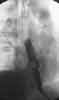

On hospital day 17, a follow-upesophagram showed that the esophagealperforation had resolved and a roundfilling defect in the distal esophagus persisted,which suggested the presence ofa foreign body (Figure 3). An esophagogastroduodenoscopyrevealed a pillwithin a plastic casing lodged in theesophageal mucosa at the site of theperforation (Figure 4). The dime-sizewrapped pill was removed endoscopicallywithout complications. The patientwas able to tolerate a clear dietand was discharged from the hospital 2days later.

Figure 3